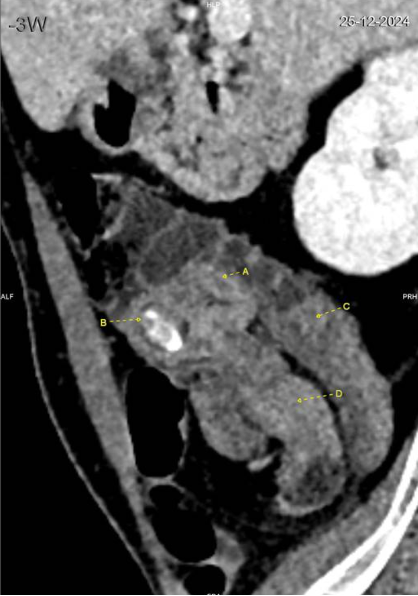

Le CT scanner abdominal montre une invagination iléo-cæcale sur environ 8 cm, sans signe de souffrance intestinale (absence de pneumatose pariétale ou de liquide libre). La valve iléo-cæcale présente un épaississement circonférentiel discrètement irrégulier, accompagné d’une calcification de 17 mm (stercolithe). L’appendice est non distendu, et aucune adénomégalie suspecte n’est observée.

Les symptômes sont souvent aspécifiques, ce qui complique le diagnostic. Les patients peuvent se plaindre de douleurs abdominales intermittentes, de nausées, de vomissements ou présenter un tableau d’occlusion intestinale aiguë dans les formes avancées. Une hématochézie peut également survenir, bien que moins fréquente. Le diagnostic repose principalement sur l'imagerie. Le scanner abdominal est l'examen de choix, avec une sensibilité dépassant 90%, montrant des images caractéristiques en "cible ou donut" ou en "sandwich" selon l’orientation de la coupe. L'échographie, bien que moins fréquemment utilisée chez l'adulte, peut révéler des signes similaires. La coloscopie est utile pour identifier une éventuelle lésion tumorale.